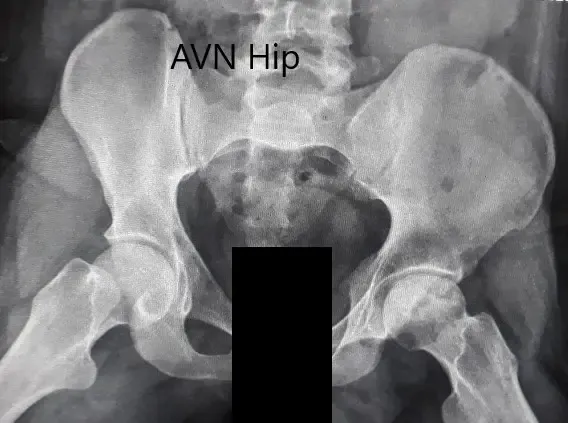

Imaging studies obtained in the form of an X-Ray suggested sclerosis of the left head of the femur. There were marked acetabulum changes. An MRI was further obtained suggesting avascular necrosis of the superior lateral head of the femur with changes in the acetabulum. There was marked hypointense areas on both T1WI and T2WIs.

Preoperative X-ray of the pelvis with both hips in the frog-legged lateral view showing AVN of the Left Hip.